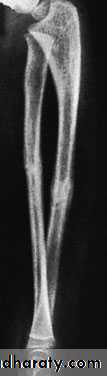

A-CHILDREN:In children, closed treatment is usually successful because the tough periosteum tends to guide and then control the reduction. The fragments are held in a well-moulded full-length cast, from axilla to metacarpal shafts (to control rotation). The cast is applied with the elbow at 90 degrees. The position is checked by x-ray after a week and, if it is satisfactory, splintage is retained until both fractures are united (usually 6–8 weeks).

Occasionally an operation is required, either if the fracture cannot be reduced or if the fragments are unstable. Fixation with intramedullary rods is preferred, but they should be inserted with great care to avoid injury to the growth plates. Alternatively, a plate or K-wire fixation can be used.